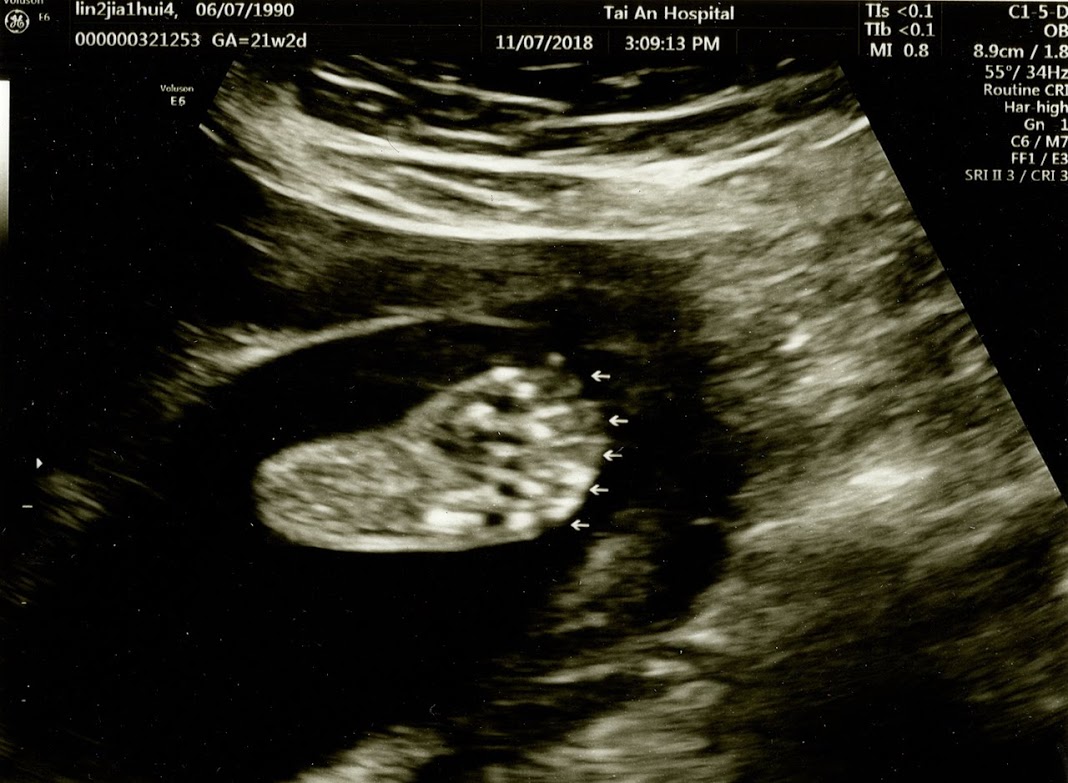

▲如上圖,寶寶用手遮住了臉,但令我們沒想到的事是原來寶寶偷偷地在羊水內重訓,他已經練出二頭肌了???

這次的檢驗都很正常,除了心臟有照到”小白點”!!!??? 醫師說現在亞洲人照到”小白點”的比例愈來愈高,而且亞洲人出現的機率幾乎是歐美族群的兩倍以上! 所以其實包括許多歐美先進國家,大家早已不把心臟”小白點”當作是一個單獨的唐氏症指標了! 加上我的初期篩檢屬於低風險群,基本上不用去做羊膜穿刺或非侵入性檢查(NIPS)! 聽完醫師的這一番話,我們便放心了不少!?